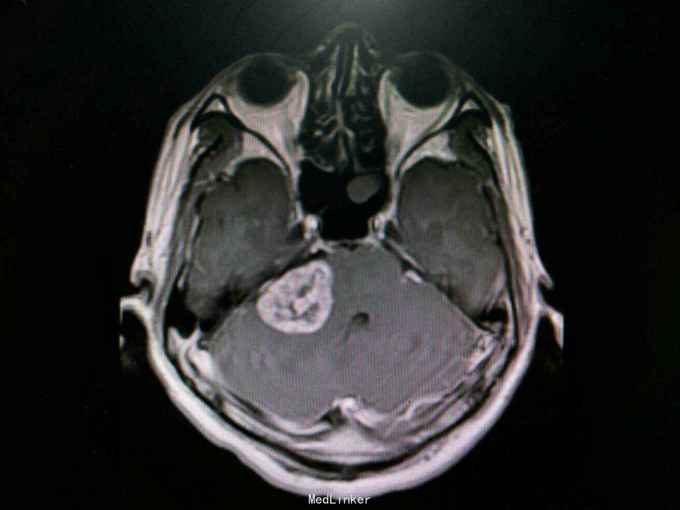

查体:生命体征平稳。神经系统检查提示:Ⅴ颅神经:右侧面部感觉稍减退,张口下颌无偏歪 。Ⅷ颅神经:右侧听力较左侧减退,无眩晕 。外院检查示行磁共振检查提示:右侧桥脑小脑角占位:听神经鞘瘤?辅助检查:颅脑MRI检查提示:右侧桥小脑角处可见类圆形占位性病变,边界清,形态规则,大小约24.8mm×33.8mm。右侧桥小脑角区占位,考虑听神经鞘瘤。

诊断:听神经鞘瘤 处理:右侧枕下乙状窦后入路听神经瘤切除术